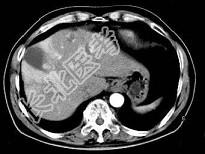

- 单项选择题根据所提供的图像,最可能的诊断是 ( )

A、肝内多发血管瘤

B、肝多发血管瘤并肝癌

C、多发肝囊肿

D、胆管细胞癌

E、以上都不是